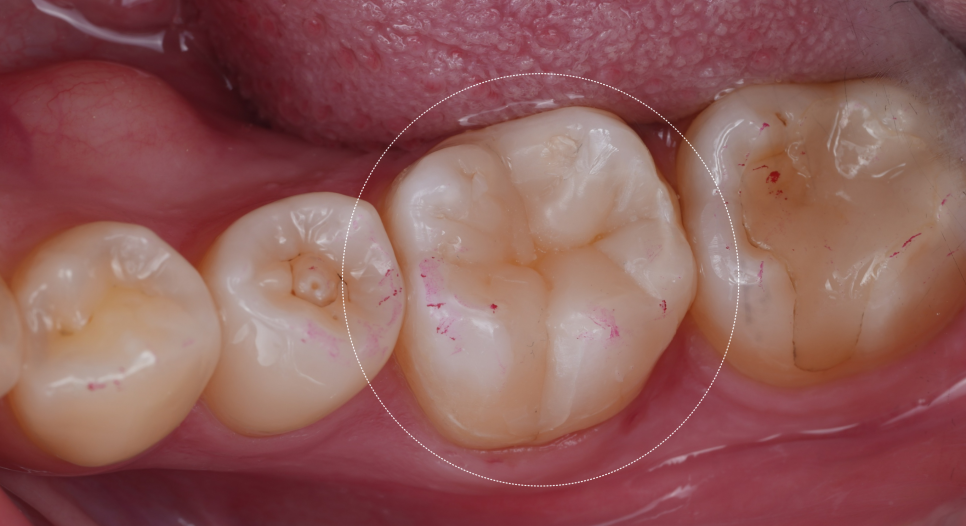

기존 인레이치료 하방으로 틈이 생겼고, 그 틈을 따라 2차 충치가 진행되었다고 합니다.

그래서 B 치과에서 치료를 권했는데.. 해당 부분만 레진으로 덧댄 상태였어요.

촬영일 : 251124

치아 가운데 하얗게 덧댄 것... 보이시죠?

심지어 레진으로 때운 곳도 온전치 않아 보이더라고요..^^;

큐레이를 통해 확인해 봐도 인레이치료 한 경계를 따라 붉은빛으로 문제가 있다는 것을 보여주네요.

큐레이는 특정 파장의 푸른 가시광선을 치아에 비추면 세균이 많은 부위에 붉은 형광빛을 띠어요.